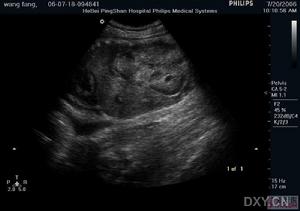

(6)B超顯示雙腎有為數眾多之暗區。

(1)及早發現病情:據統計,多囊腎有60%-70%的遺傳傾向,且男女患病機會大致相等。所以,在一個有多囊腎家庭史的家庭中可有多人同時患病。由於多囊腎發病一般在25-35歲才開始出現症狀,有的病人甚至在出現腎功能衰竭的症狀後才被發現。故對有多囊腎家庭史的人員,宜做普查與定期隨訪,以便早期發現,及時治療。目前常用的B超、CT、MRI(核磁共振)等檢查手段,均可作出對多囊腎的診斷。血肌酐、尿素氮能反映出腎功能損害的程度與病情的發展階段,故宜作定期檢查。基因診斷方法,可了解妊娠早期胎兒的遺傳情況,對提高優生率有一定幫助。